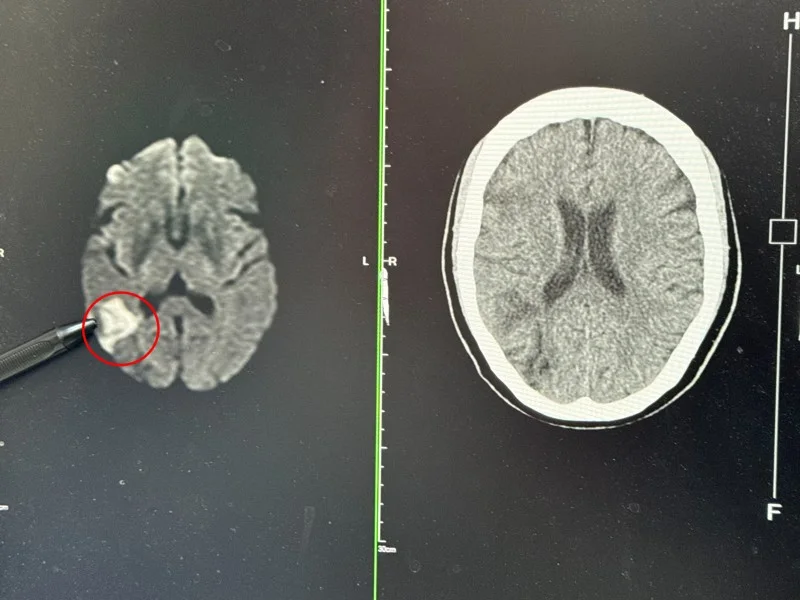

直到最近左手開始麻木、口齒略不清楚,她才到李綜合醫院求診。醫師張峻誠一聽症狀,立即懷疑是中風,安排電腦斷層與核磁共振,果然發現右側中大腦動脈阻塞,而第一次發生視力模糊時,就是她第一次中風的時點。

常見的大眾印象中,中風一定會「臉歪嘴斜、走路不穩」,但張峻誠指出,這名婦人屬於「非典型中風」,阻塞位置特殊,所以沒有典型的症狀。她走路正常、意識清楚,只有視力模糊與輕微麻木,反而讓她誤以為只是疲勞或眼睛問題。